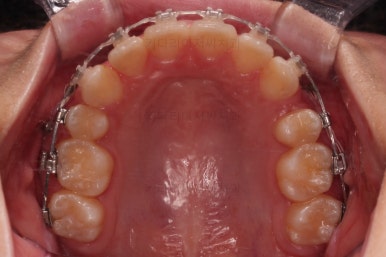

윗니는 틈을 점점 줄여가고요.

아랫니는 중간에 오히려 틈이 생기고 있죠?

이런 효과로 위아래 앞니는 급속도로 가까워지게 됩니다.

아랫니는 이후에 어금니를 앞으로 당겨오면서 빈공간을 줄여 나갑니다.

교합이 점점 맞아가네요.

윗니 뽑은 자리도 거의 다 줄었습니다.